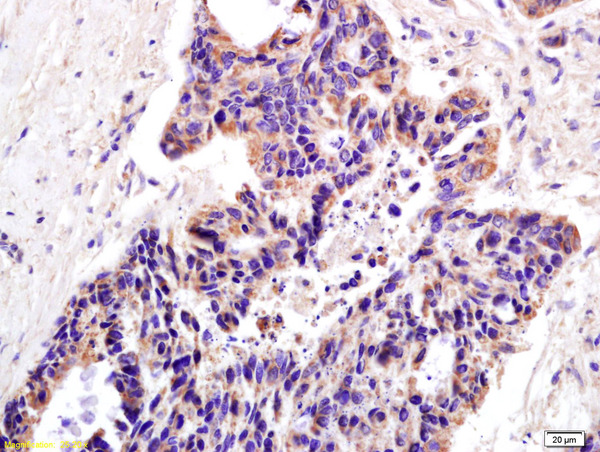

IHC-P analysis of human colon carcinoma tissue using GTX51780 XAGE2 antibody.

Dilution : 1:200